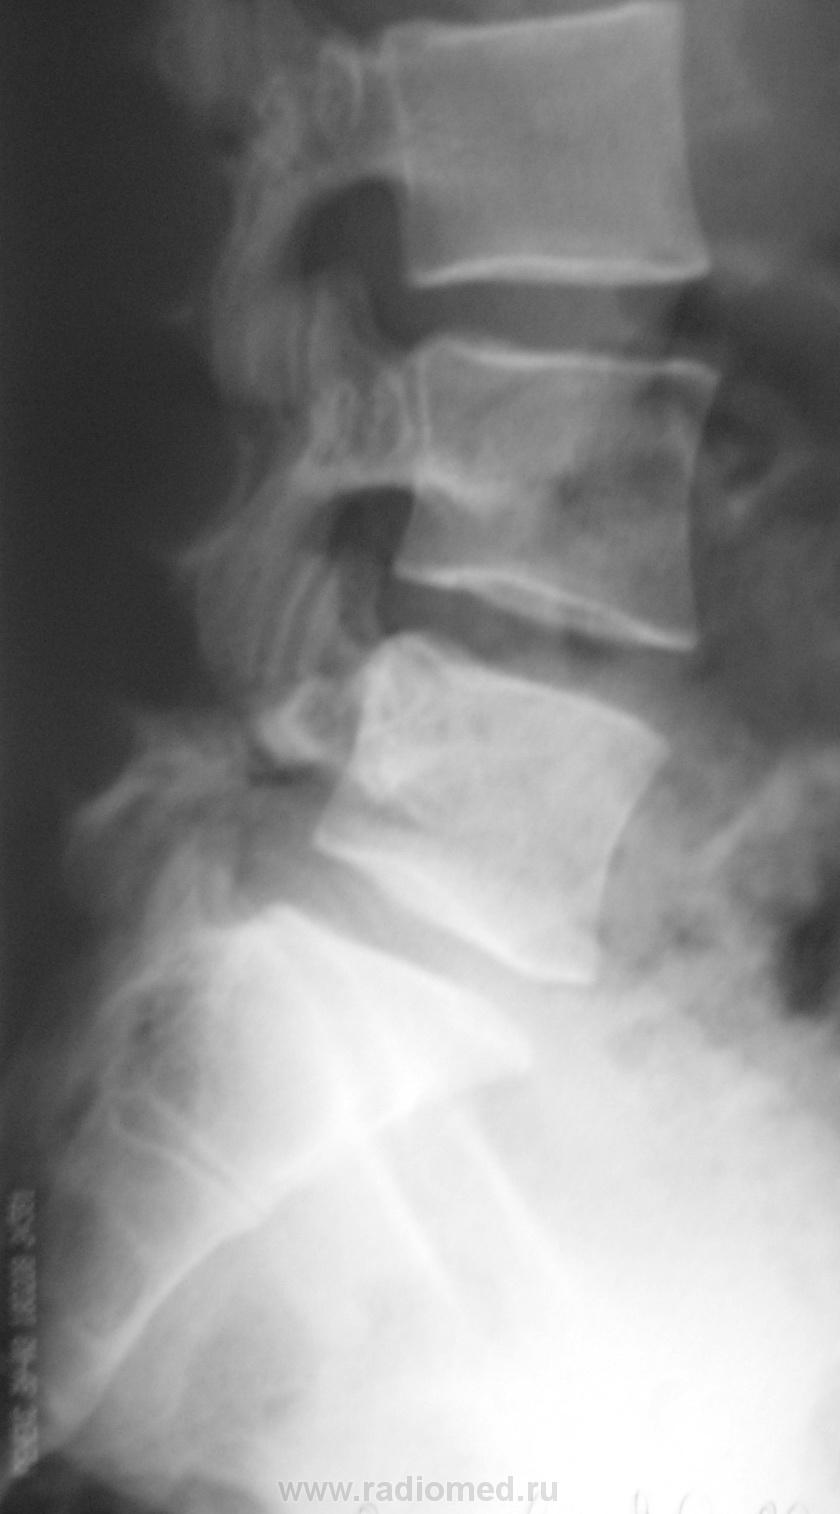

Пол пациента: Женский пол Тип патологии: Врожденная патология Область исследования: Скелетно-мышечная система Методы исследования: Rg Молодая женщина пришла на снимок поясничного отдела. Другая женщина, которая занимается рукопашным боем, обратилась с жалобами на боли в пояснице, после неудачного броска. https://radiomed.ru/sites/default/files/styles/case_slider_image/public/user/712/sl274202.jpg?itok=nrVgJub5 https://radiomed.ru/sites/default/files/styles/case_slider_image/public/user/712/sl274211.jpg?itok=ON6uvgKI https://radiomed.ru/sites/default/files/styles/case_slider_image/public/user/712/sl274212.jpg?itok=NmuMvaE1 https://radiomed.ru/sites/default/files/styles/case_slider_image/public/user/712/sl274213.jpg?itok=nP2dg6tE ID:18475 Пт, 27/01/2012 - 18:10 #1 Фаина Не на сайте Был на сайте: 2 года 11 месяцев назад Зарегистрирован: 14.12.2008 - 16:51 Публикации: 323 В первом случае, кроме остеохондроза и несросшихся апофизов, честно говоря, ничего критичного" не увидела. А во втором случае, не спондилолиз ли в L5?! Пт, 27/01/2012 - 18:17 #2 Наталия Не на сайте Был на сайте: 8 лет 7 месяцев назад Зарегистрирован: 30.07.2008 - 13:24 Публикации: 538 Во втором случае вероятнее спондилолиз. Пт, 27/01/2012 - 18:25 #3 Глазков Игорь А... Не на сайте Был на сайте: 9 месяцев 1 неделя назад Зарегистрирован: 19.12.2008 - 20:41 Публикации: 1597 Шморля в каудальной части тела позвонкаТ12 Прийди к Себе Пт, 27/01/2012 - 21:15 #4 И.Бондаренко Не на сайте Был на сайте: 3 дня 7 часов назад Зарегистрирован: 13.09.2011 - 22:55 Публикации: 9206 Случай №1. Грыжа Шморля Т12, несросшиеся апофизы L2,5 или обызвествившиеся грыжи дисков. Случай №2. Спондилолиз дужки L5. Ср, 01/02/2012 - 21:08 #5 Natalja Не на сайте Был на сайте: 13 лет 10 месяцев назад Зарегистрирован: 27.01.2012 - 22:08 Публикации: 4 Глазков Игорь Артурович wrote: Молодая женщина пришла на снимок поясничного отдела. Другая женщина, которая занимается рукопашным боем, обратилась с жалобами на боли в пояснице, после неудачного броска. В первом случае смущает L2, травмы не было? Чт, 02/02/2012 - 14:35 #6 Глазков Игорь А... Не на сайте Был на сайте: 9 месяцев 1 неделя назад Зарегистрирован: 19.12.2008 - 20:41 Публикации: 1597 травму отрицает Прийди к Себе

Во втором случае вероятнее спондилолиз.

Случай №2. Спондилолиз дужки L5.